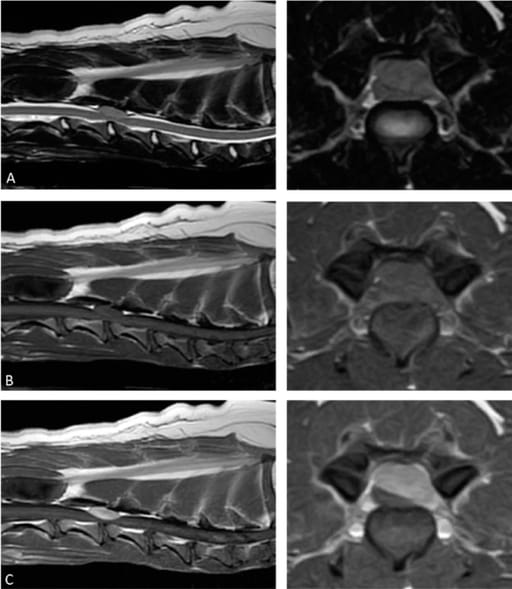

This figure is the preoperative magnetic resonance imaging of the epidural mass lesion. The mass lesion is isointense to the spinal cord parenchyma on T2-weighted images: (A) T1-weighted images; (B) the postcontrast T1-weighted images reveal a homogeneous enhancing lesion with spinal cord compression; (C) no abnormality is observed in the adjacent bone.